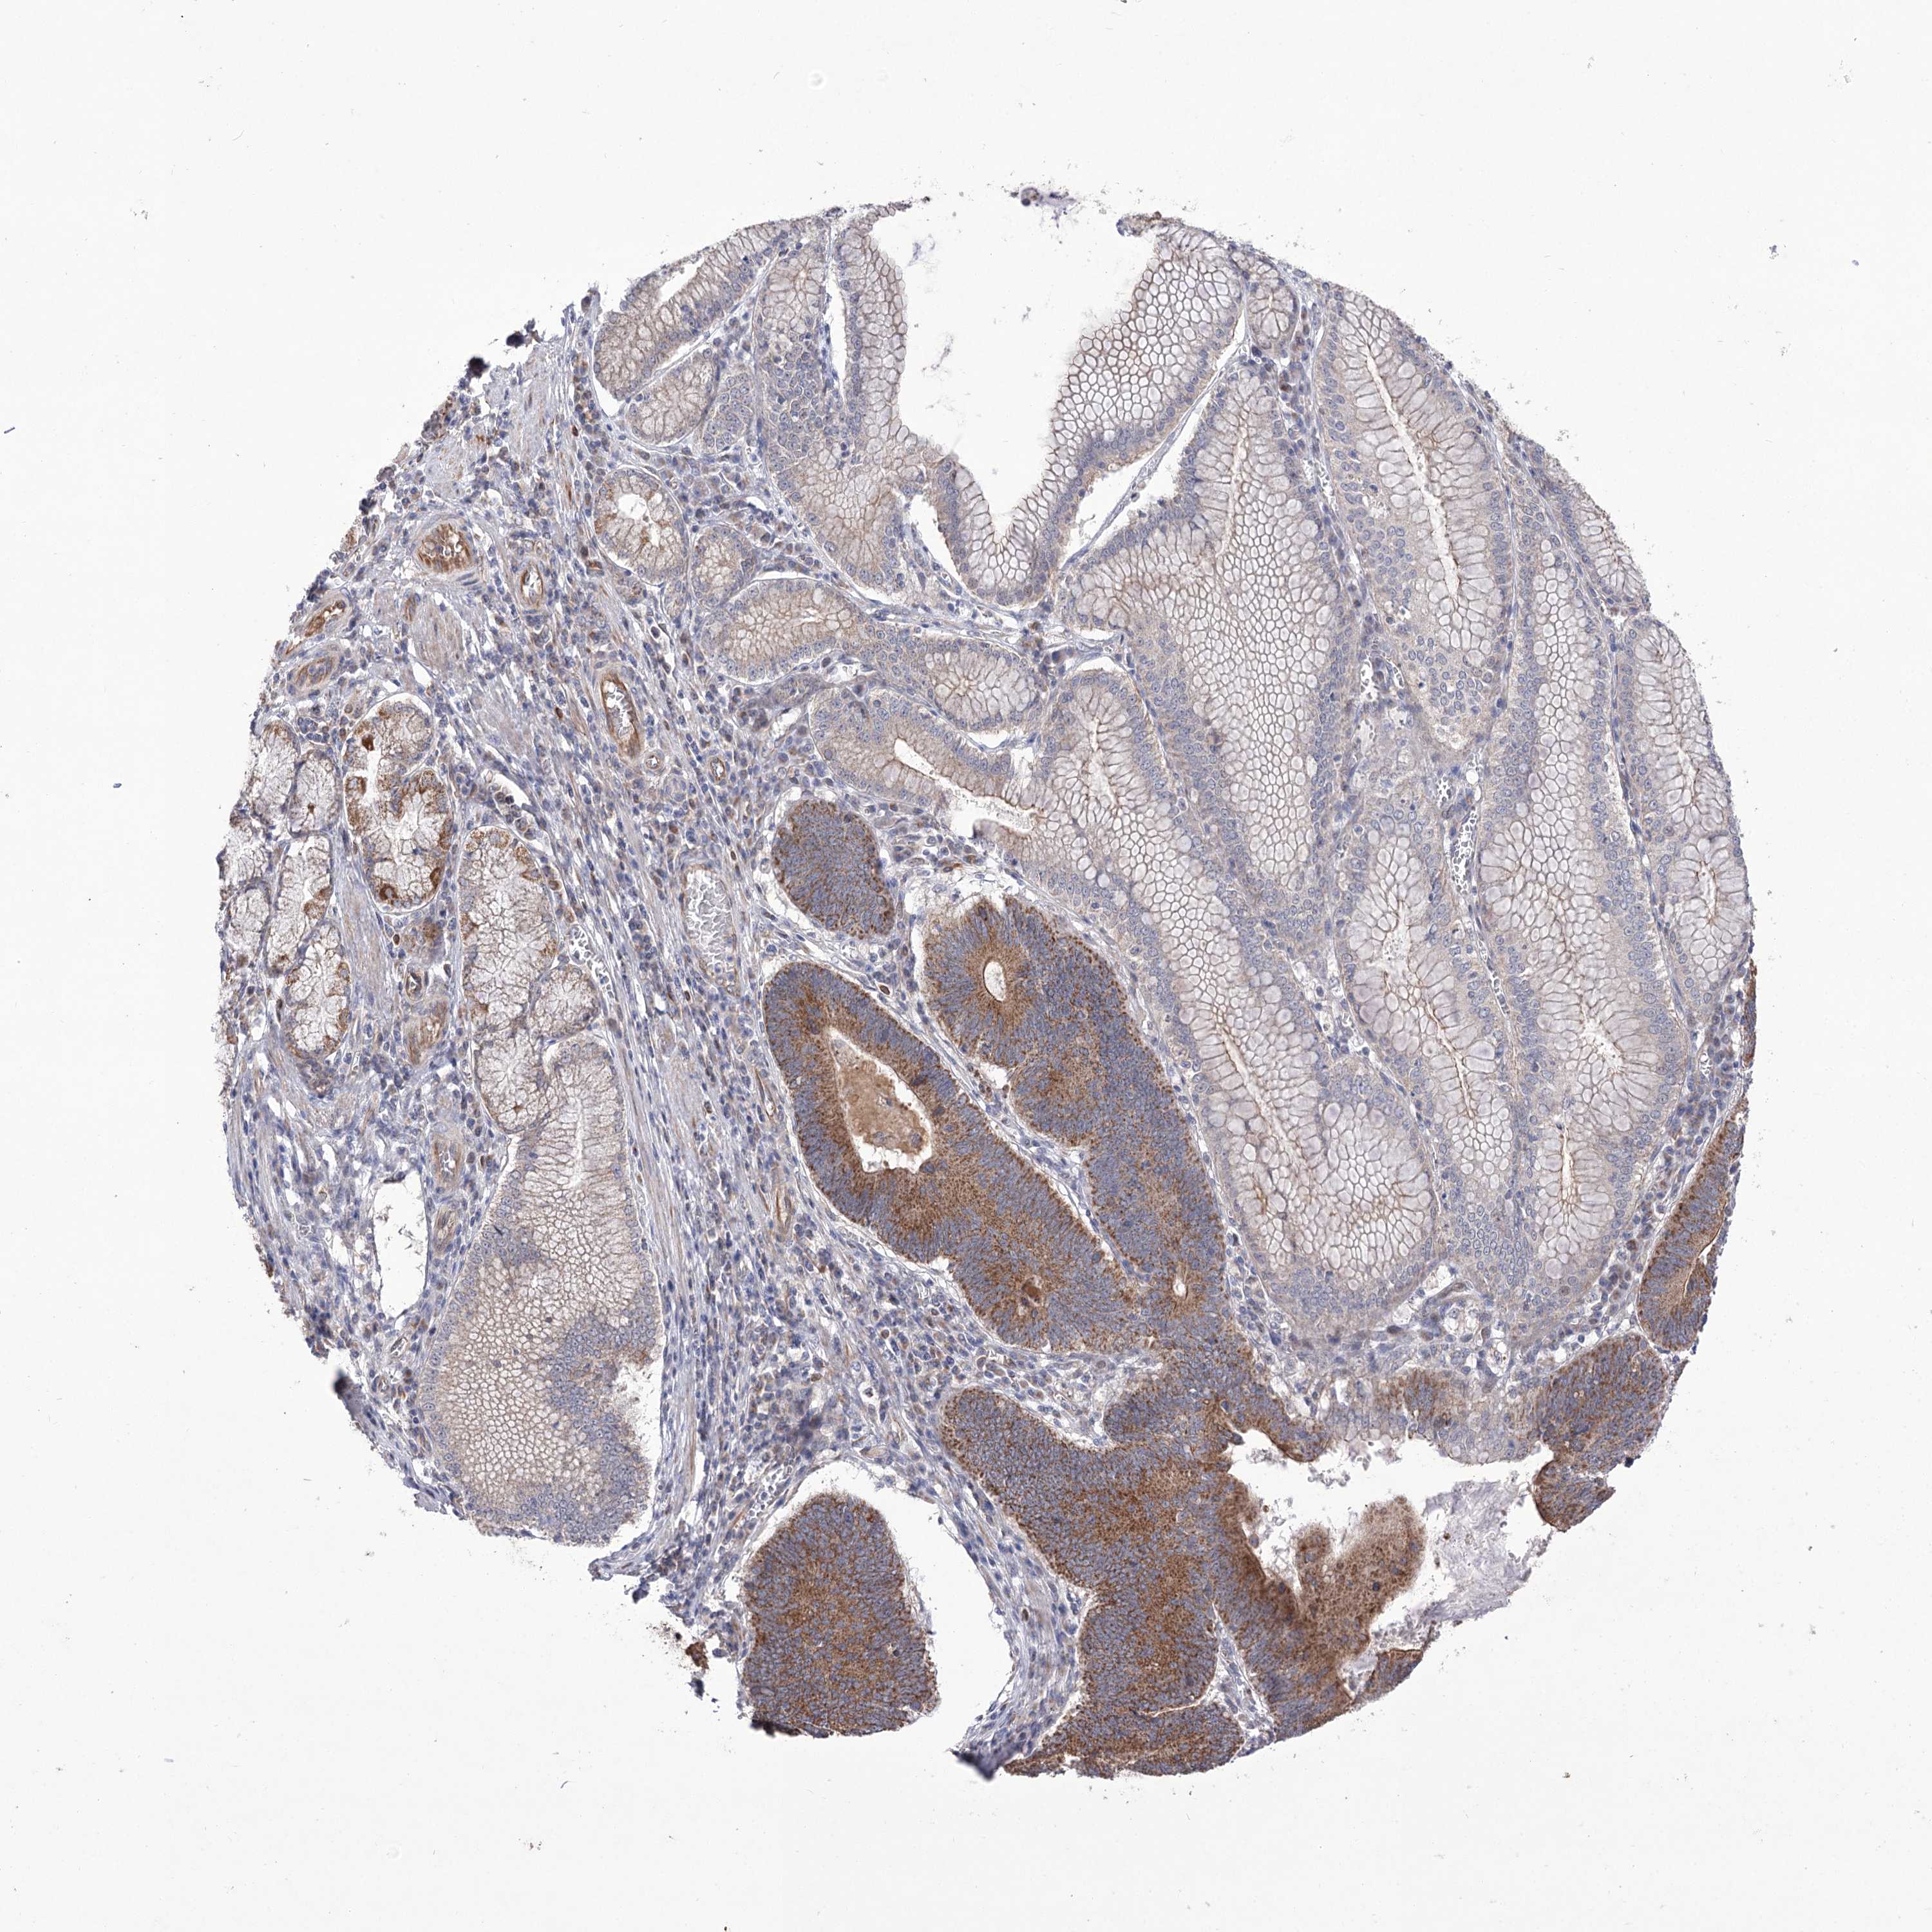

STOMACH CANCER - Protein expressioni

A mouse-over function shows sample information and annotation data. Click on an image to view it in a full screen mode. Samples can be filtered based on level of antibody staining by selecting one or several of the following categories: high, medium, low and not detected. The assay and annotation is described here.

Note that samples used for immunohistochemistry by the Human Protein Atlas do not correspond to samples in the TCGA dataset.

Antibody stainingi

Antibody staining in the annotated cell types in the current human tissue is reported as not detected, low, medium, or high, based on conventional immunohistochemistry profiling in selected tissues. This score is based on the combination of the staining intensity and fraction of stained cells.

Each image is clickable and will lead to virtual microscopy that enables deeper exploration of all samples and also displays staining intensity scores, fraction scores and subcellular localization as well as patient and tissue information for each sample.

Antibody HPA038306

Staining

High

Medium

Low

Not detected

Intensity

Strong

Moderate

Weak

Negative

Quantity

>75%

75%-25%

<25%

None

Location

Nuclear

Cytoplasmic/membranous

Cytoplasmic/membranous,nuclear

Adenocarcinoma, NOS